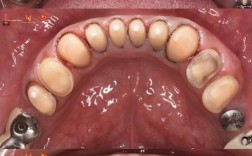

- 术后正畸:术后1-2周开始佩戴矫治器精细调整咬合,关闭剩余间隙,协调牙齿与骨骼关系,持续6-12个月。